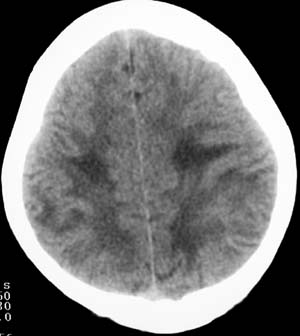

两侧颞枕叶脑白质区多发斑片状低密度灶,考虑脑白质病变;肾上腺脑白质营养不良可能大。

1,发病年龄相符,5-10y。2,临床有视、智力改变。3,病灶发病位置相符;大脑后部白质,侧室三角区周围,对称。

两侧脑室后角旁、丘脑、放射冠、颞顶叶呈对称性片状低密度影,脑室系统、环池、四叠体池、脑桥小脑角池偏大。

病灶从后向前发展,结合临床表现,首先考虑:肾上腺脑白质营养不良。

两侧脑室后角旁、丘脑、放射冠、颞顶叶呈对称性片状低密度影。